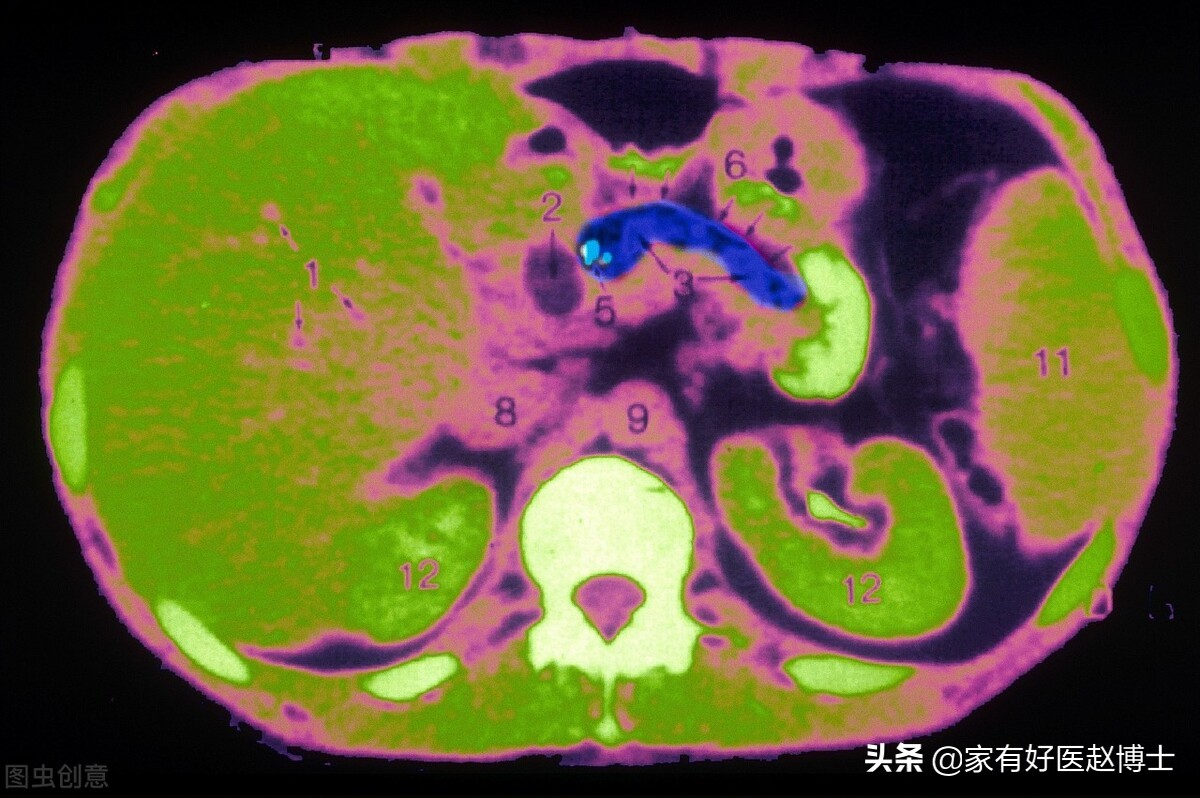

但是,当钙质沉积在本不应该含有固态钙的组织器官、血管等部位时,我们就称其为“病理性钙化”。在体检当中,一般是通过超声检查、X光片或CT扫描等医学影像学技术来发现这些钙化。

第一个要说的是肝脏内的钙化,这个在体检的肝脏超声检查里经常会遇到,有时候肺部CT扫描也可以看到一部分肝脏,也能发现这个问题。

大多数情况下,肝内钙化都是继发于一些其他的疾病,多形成于这些疾病的稳定期或愈合期。最多见的是与肝内胆管结石有关,还有比如寄生虫感染、慢性肝炎、肝内胆管炎、肝硬化等也可以引起。尽管,在极少数情况下,一些肝内的肿瘤也可以出现钙化表现,但是,这种情况往往都会伴随有肿瘤引起的一系列其他明显异常。

所以,大部分在体检当中发现的肝内钙化都属于良性,长期来看比较稳定,一般不需要药物治疗更不需要手术切除。只不过,当肝内钙化同时合并有胆管炎、明显的肝内胆管结石或者肝血管瘤时,还是建议要找肝胆科专科医生看一下的。